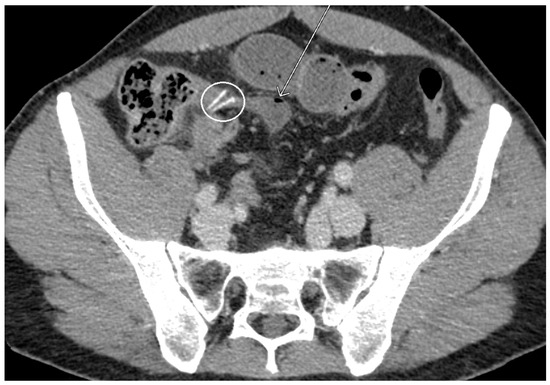

2. Case Presentation